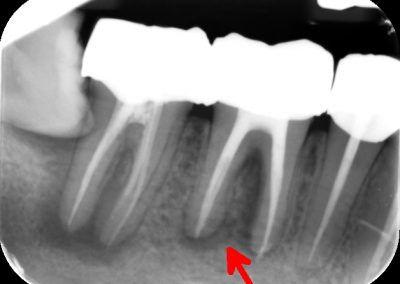

During the consultation, the dentist will first listen to your concerns and carry out appropriate tests to identify the right tooth that is causing pain. As a part of the diagnosis, your dentist will carry out various clinical tests to identify the right tooth and will take some radiographs which can aid in the diagnosis.

An access cavity is placed on the surface where the patient bites, to reach the root canals of the tooth. Once all the canals are identified, small files are used to remove the infected pulp.

Files of different sizes are used to eliminate bacteria and infection and to shape the canals. The canals are disinfected thoroughly with irrigants and later the canals will be sealed in 3 dimensions with a special medicament called gutta-percha to prevent reinfection of the tooth and the access cavity will be sealed with a temporary filling.